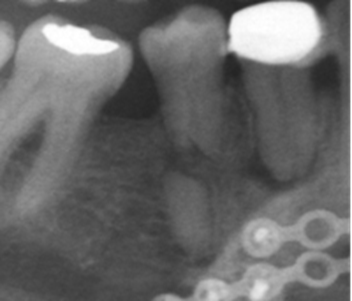

Los resultados mostraron que en el 48 % de la población se encontró algún hallazgo relacionado con la pulpa dental, con frecuencias similares entre hombres y mujeres, siendo el tratamiento endodóntico el más frecuentemente encontrado (Tabla 1, Fig. 1). El rango del número de endodoncias por radiografía fue de 1 a 18. El 86,4 % de las radiografías presentaron de 1-5 endodoncias, 11,4 % de 6-10 y el 2,2 % de 11-18. La presencia de zona radiolúcida periapical seguida por la reabsorción (Fig. 2), fueron los siguientes hallazgos más frecuentes. (Tabla 1)

La presencia de hallazgos compatibles con reabsorción externa se observó en 27 radiografías con alta variación entre género y edad. Se sabe que la reabsorción externa ha sido relacionada con varios factores, pero gran parte se debe a tratamientos ortodónticos siendo una condición irreversible y que afecta negativamente el pronóstico de los dientes19.

Las fracturas dentales se presentaron en baja frecuencia en el presente estudio, a pesar de ser consideradas por otros autores como un problema de salud pública por su alta prevalencia especialmente en niños y adolescentes, aunque la radiografía panorámica no permite estudios de gran precisión sobre este tema20.